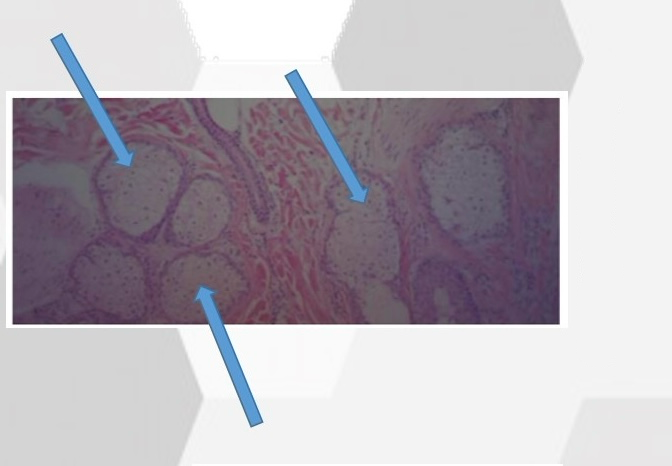

What is this gland

Sebaecous Glands

Name this gland

Eccrine (Sweat) Glands